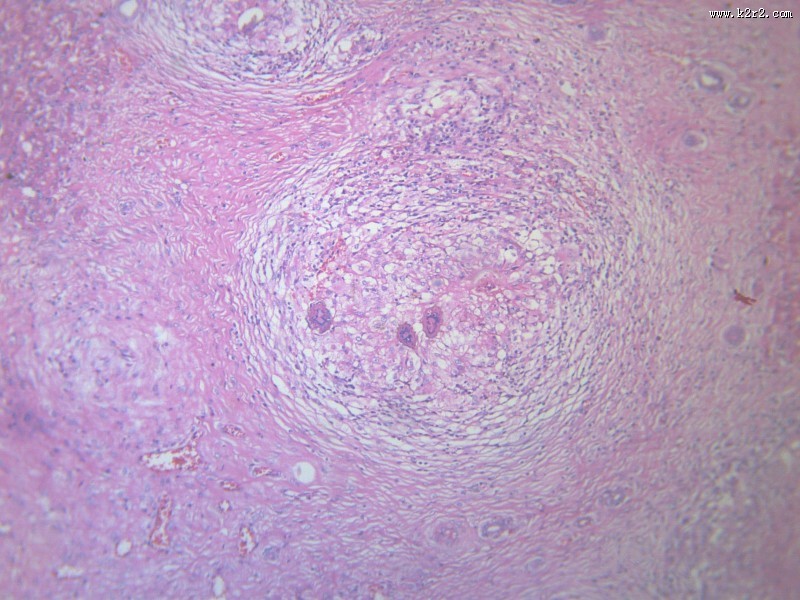

首页 > 其他类别 > 虫卵肉芽肿(12张) > 虫卵肉芽肿 第8张

虫卵肉芽肿 - 第8张